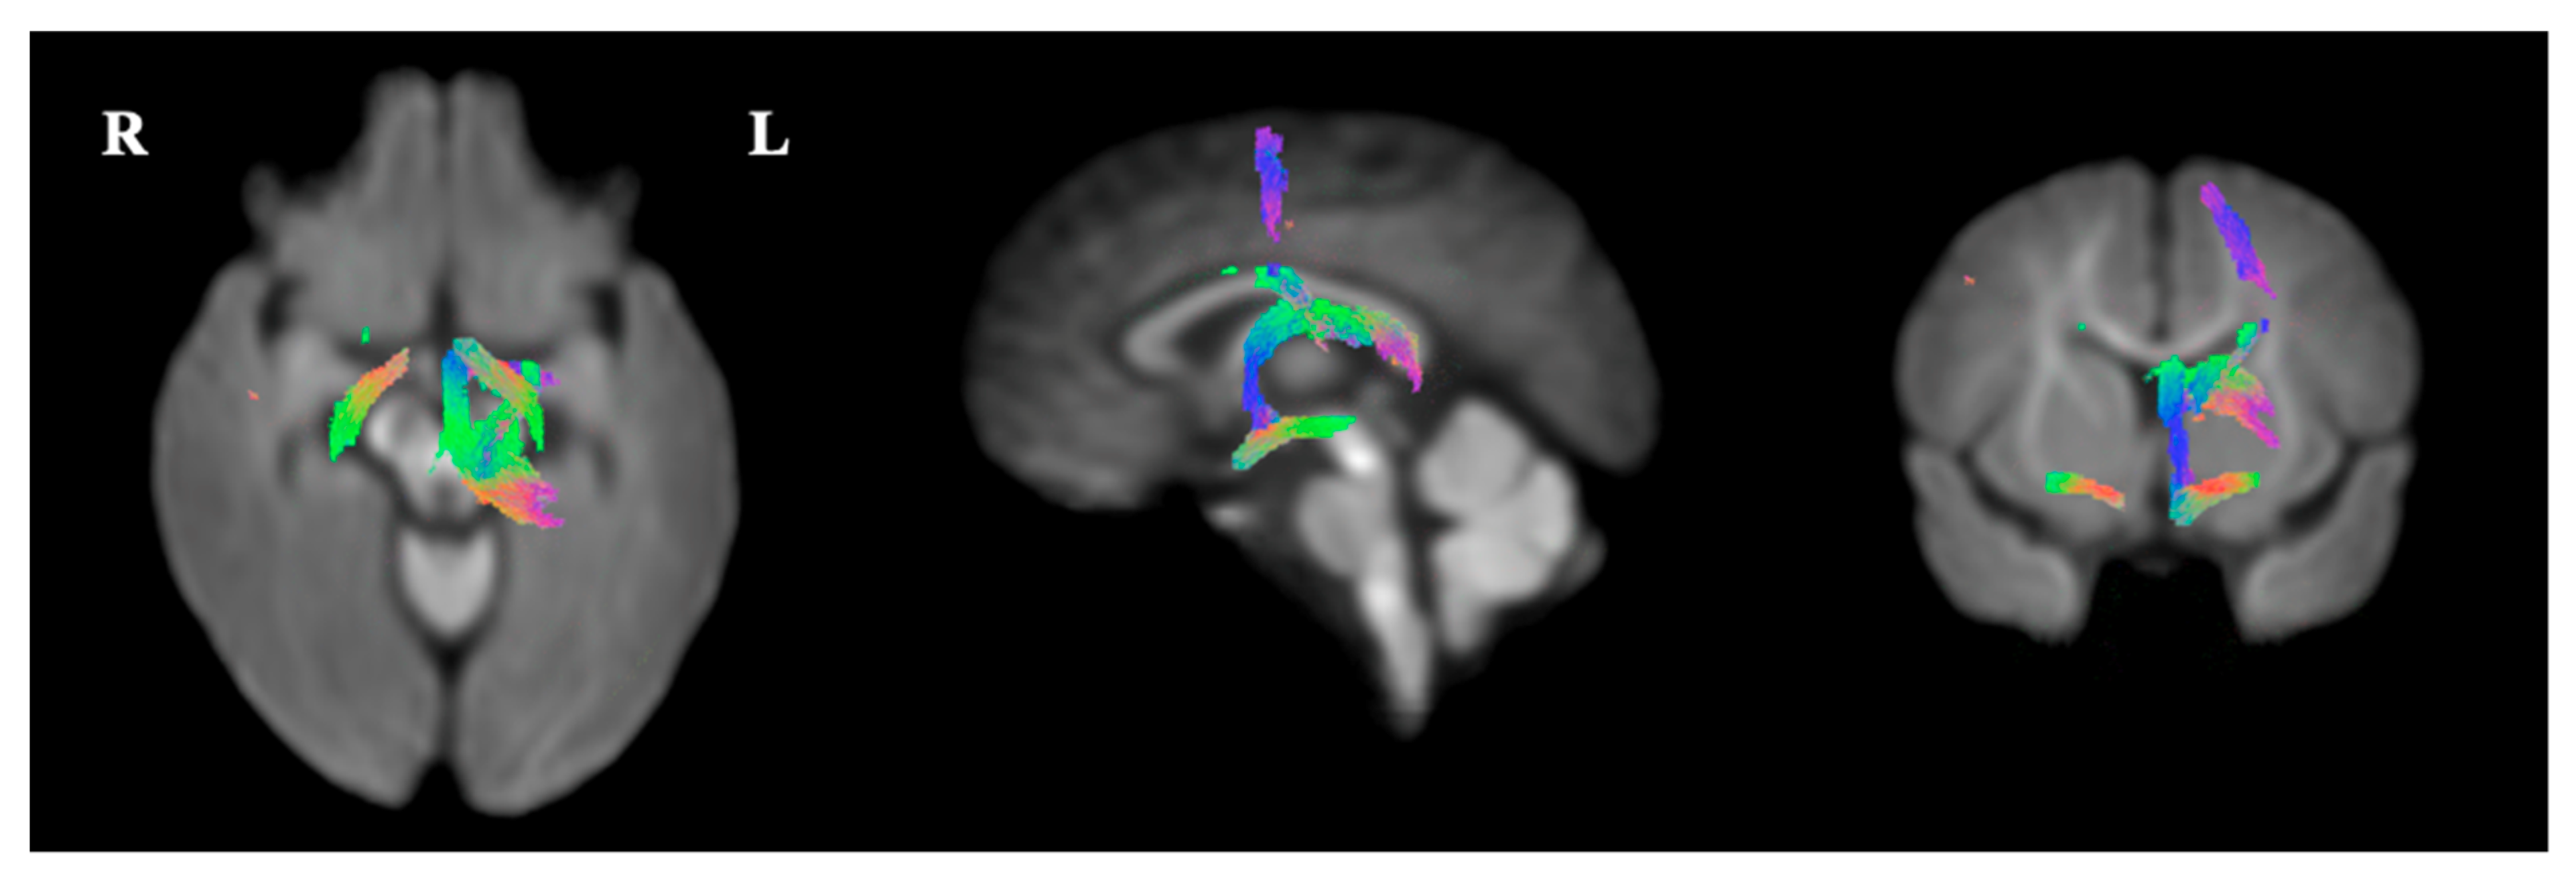

2.5.3. Fixel-Based Analysis

3.4. Fixel-Based Diffusion